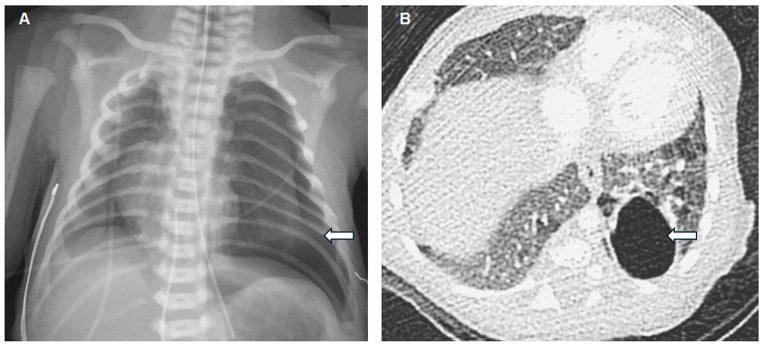

肺囊性病变在婴儿中并不常见,并且由于与其他囊性肺疾病的放射学特征重叠,可能会给诊断带来挑战。我们报告2例婴儿左肺囊性病变。最初的高分辨率计算机断层扫描(HRCT)提示鉴别诊断,包括气膨出、I型先天性肺气道畸形(CPAM)或孤立性囊性淋巴管瘤。通过左下叶切除术和病变切除后的组织病理学检查获得明确诊断。这些病例强调了准确诊断肺囊性病变的挑战,因为单独成像的局限性。

Pulmonary cystic lesions in infants are uncommon and can present diagnostic challenges due to overlapping radiologic features with other cystic lung conditions. We present 2 cases of left lung cystic lesions in infants. Initial high-resolution computed tomography (HRCT) suggested differential diagnoses, including pneumatocele, type I congenital pulmonary airway malformation (CPAM), or a solitary cystic lymphangioma. Definitive diagnosis was achieved through histopathological examination after left lower lobectomy and resection of the lesion. These cases highlight the challenges in accurately diagnosing pulmonary cystic lesions, given the limitations of imaging alone.